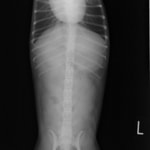

4歳 アメリカンショートヘアー

主訴:3日前から嘔吐が続き、食欲も落ちてきたのこと。

対症療法(症状に対する治療)に反応しないため、精査を実施。

一般血液検査:問題なし

単純レントゲン検査:胃内ガス陰影・腸内ガスが少量認められる。

嘔吐が改善しないため、消化管バリウム造影検査を実施。

以下、

消化管バリウム造影レントゲン

バリウム造影3時間経過するも、胃内からバリウム排泄なく同日内視鏡検査を実施。

内視鏡検査結果:内視鏡下にて、バスケット鉗子を用いて摘出。

症例は、机の上に置いていたピスタチオのお菓子を誤飲していました。その後の経過は良好です。本症例は、内視鏡下にて摘出ができましたが、球状・立体などの大きな異物は、腸の途中で詰まりやすく、内視鏡下での摘出が困難な場合もあります。その際は、開腹下にて腸内の異物を摘出しなくてはなりません。動物たちは、思わぬ物を誤飲することがあります。お留守番時・就寝時は、誤飲をしやすい時間帯ですので注意しましょう。